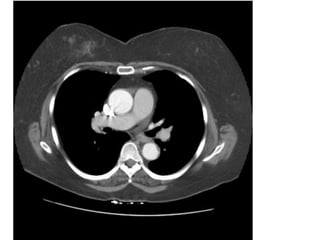

Figure 25c. PE cấp ở bn nam 59 tuổi.

(c) CT scan (window width = 700 HU, window level = 100 HU) cho thấy

thrombus ở đm liên thùy (P) và nhánh trong của đm thùy giữa (P).

- Hình 25 cho thấy ở các cửa sổ khác nhau có hiệu quả phát hiện huyết khối

khác

nhau.

33